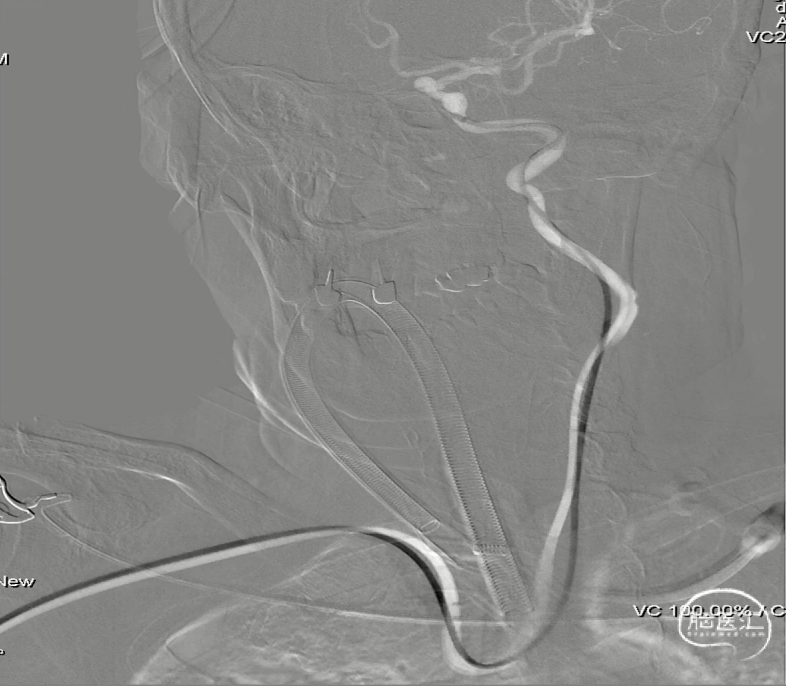

经桡动脉入路,0.035''泥鳅导丝配合SIM导管携远端通路导引导管置于颈内动脉海绵窦段。

导管到位后,放大倍率下再次行造影,经校准后测量得出:靶动脉瘤远端血管直径2.93mm,近端血管直径2.83mm,拟释放节段血管长度约16.1mm。更换工作角度,再次校准后确认远端及近端血管直径。

Phenom™ 27 微导管置于大脑中动脉M2段。

微导管到位

根据血管测量结果,选择一枚Pipeline™ Flex with Shield Technology™ 血流导向密网支架 2.75×20mm,支架输送顺利,随后回撤微导管,将支架头端于大脑中动脉M1段血管平直处打开。

支架输送

支架头端打开

见支架头端打开良好后,回撤系统,将支架头端锚定于A1开口处近端,透视及造影下确认支架头端位置理想,随后进一步通过推拉结合的方式释放支架。

支架头端释放及造影确认

支架中段释放

支架中段释放后造影确认

支架尾端释放及造影确认

常规行微导丝按摩进一步促进支架打开和贴壁。

微导丝按摩